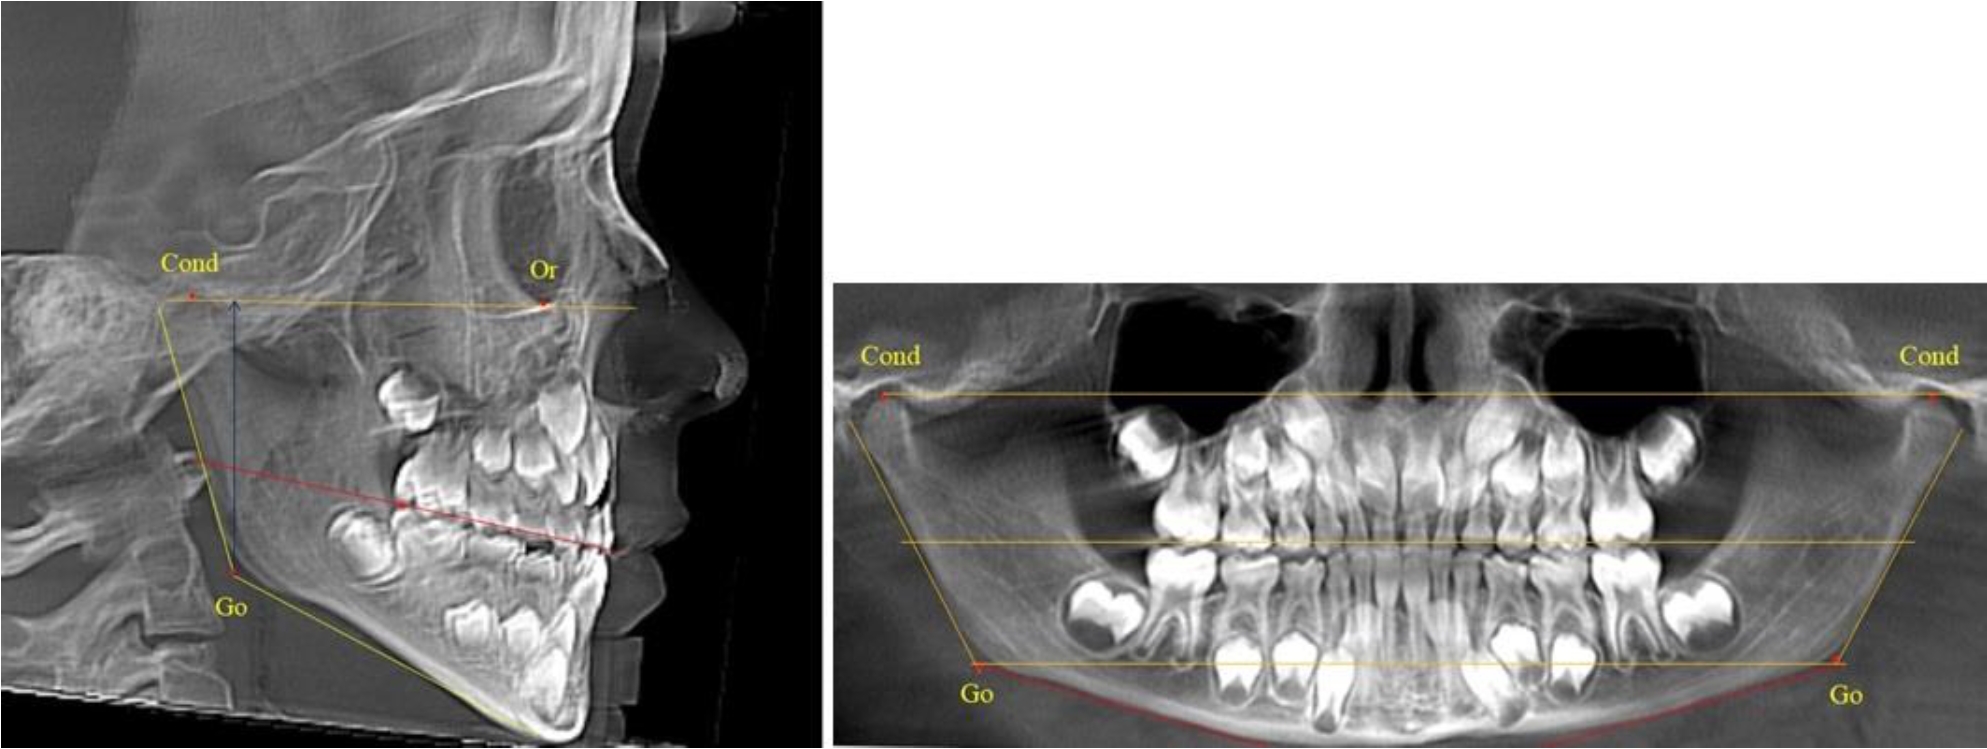

Во 2-й группе были проанализированы 11 телерентгенограмм и 11 ортопантомограмм, что составило (10,38 ± 2,96) % от числа изученных рентгенограмм. На всех рентгенограммах первые постоянные моляры были установлены в окклюзии, и произошла смена нижних медиальных резцов.

На всех парах рентгенограмм угол нижней челюсти, измеренный на телерентгенограмме, так же, как и в 1-й группе, соответствовал углу, полученному при построении угла на ортопантомограмме. Окклюзионная линия делила ветвь на два отдела (рис. 2).

Рис. 2. ТРГ и ОПТГ пациента после прорезывания первых постоянных моляров

Как на ортопантомограмме, так и на телерентгенограмме высота ветви у детей 2-й группы составляла (46,54 ± 2,87) мм, что было несколько больше, чем у детей 1-й группы (р ˂ 0,05). При этом высота верхней окклюзионно-суставной части была (25,42 ± 1,59) мм, а нижней – (21,12 ± 1,77) мм.

Таким образом, верхняя часть была несколько больше нижней, что и определяло рост обеих частей ветви.

Относительные показатели соразмерности частей ветви нижней челюсти показали, что отношение высоты верхней части ветви к нижней в среднем составляло 1,21 ± 0,12. Отношение общей высоты ветви к верхней ее части составляло 1,83 ± 0,13, а отношение общей высоты ветви к нижней ее части было 2,20 ± 0,16, и достоверных различий по относительному показателю отношения всей высоты к верхней и нижней челюсти нами не отмечено (р ˃ 0,05).